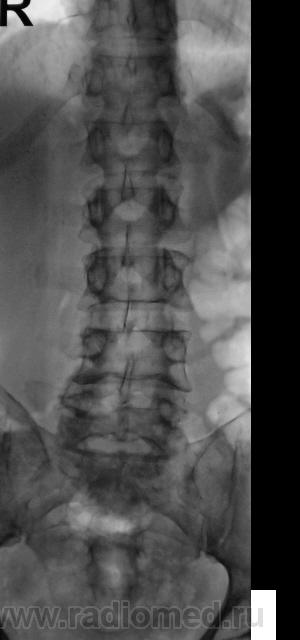

Пациент направлен на рентгенографию поясничного отдела позвоночника.

По этим снимкам нельзя исключить деструкцию Л1. Но окончательно лучше исключать не по этим.